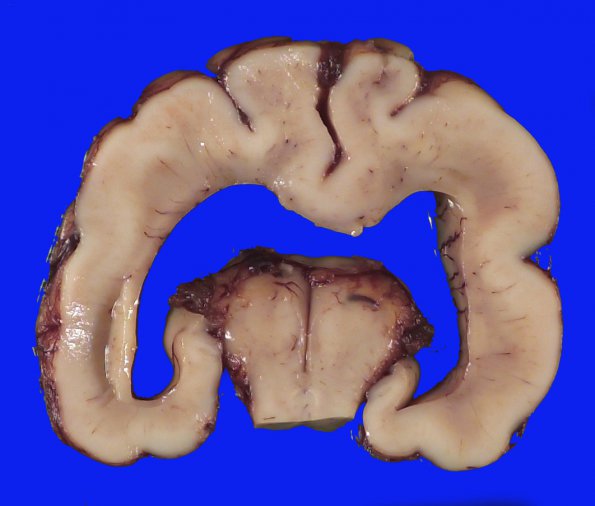

An additional section shows the thalamus is fused into a single mass. Caudally the third ventricle is represented by a partially fused space.